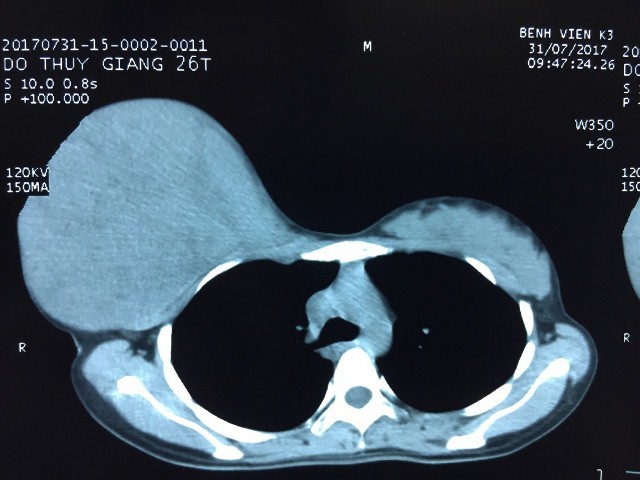

Mẹ hoãn phẫu thuật khối u tuyến vú cực lớn để sinh con

Ngay sau sinh 2 ngày, sản phụ này đã phải nhập viện điều trị vì khối u quá lớn, chiếm toàn bộ tuyến vú phải.